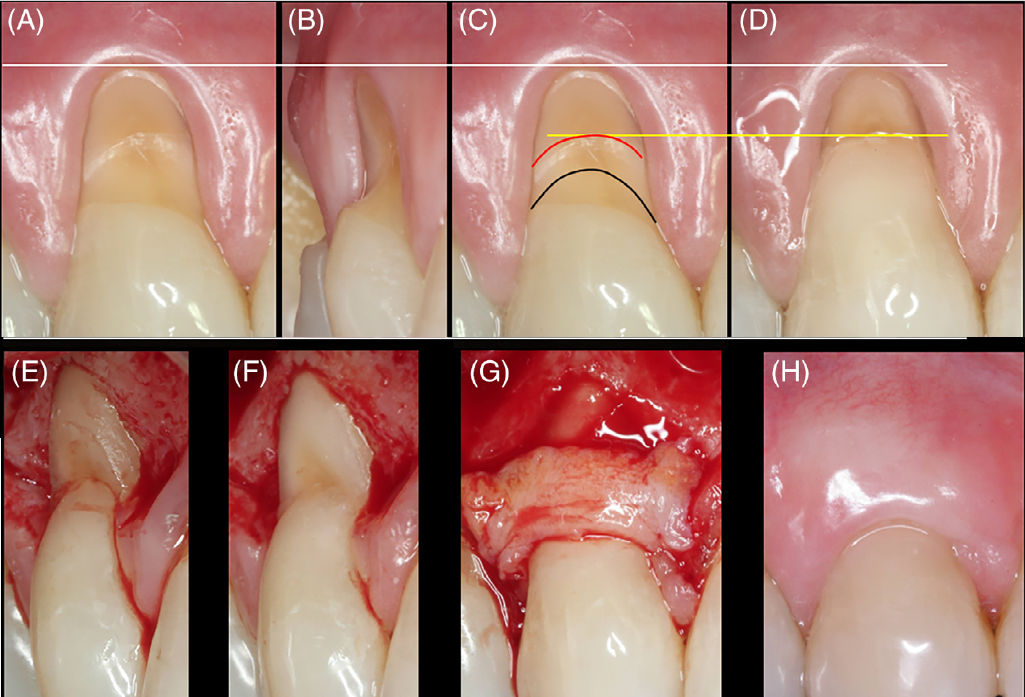

Рис 1 (A-E). Алгоритм принятия решений при лечении некариозных пришеечных поражений (NCCLs) в комбинированных дефектах (CDs)

(A, B) Вид поверхности зуба типа A−. Рецессия десны характеризуется визуализируемой цементо-эмалевой границей (CEJ) без ступеньки. Следовательно, показана хирургическая процедура покрытия корня с учётом гингивального фенотипа пациента. Дополнительных вмешательств, кроме тщательной очистки поверхности зуба перед операцией, не требуется. (C–E) Вид поверхности зуба типа A+. NCCL затрагивает только поверхность корня. CEJ интактна. Рекомендуется подход «биологической реставрации»

Вид поверхности зуба типа B−

Рис 1 (F-H). Алгоритм принятия решений при лечении некариозных пришеечных поражений (NCCLs) в комбинированных дефектах (CDs). (F–H) Вид поверхности зуба типа B−. Неглубокое NCCL распространяется на коронковую и корневую поверхности без формирования ступеньки. В большинстве случаев следует рассматривать только хирургическое покрытие корня с учётом локальной анатомии. При выраженной гиперчувствительности дентина возможно применение комбинированного реставрационно-пародонтологического подхода либо проведение лечения гиперчувствительности после хирургического вмешательства

Типичный случай рецессии десны RT1 и некариозного пришеечного поражения B+

Рис 2. Типичный случай рецессии десны RT1 и некариозного пришеечного поражения B+. (A, B) Исходная клиническая картина. Схематическое определение границ реставрации. (C) Чёрная фестончатая линия обозначает предполагаемое расположение цементо-эмалевой границы (CEJ), красная фестончатая линия — апикальный край реставрации, расположенный до 1мм апикальнее предполагаемой CEJ. (D) Вид после завершения реставрационного этапа.(E) Боковой вид реставрации после отслаивания лоскута. Обратите внимание, что профиль выхода восстановлен. (F) Апикальная ступень NCCL уменьшена после одонтопластики. (G) Соединительнотканный трансплантат (CTG) фиксирован швами. (H) Вид через 1 год наблюдения